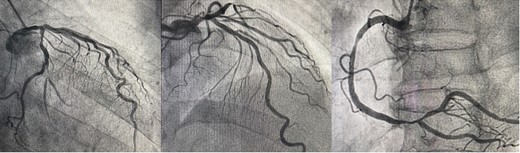

The patient was positioned by elevating in a 30° to 40° right lateral decubitus position to facilitate a widened intercostal space. The patient was intubated with a double-lumen endotracheal tube. A 10 cm left mini-thoracotomy was performed in the fourth intercostal space, with 1/3 of the incision medial to the mid-clavicular line. The ThoraTrak® MICS Retractor System (Medtronic Inc., MN, USA) was employed to achieve optimal access to the left chest and effectively visualize the internal mammary arteries. The LITA was harvested in a skeletonized fashion under direct vision, and the saphenous vein (SVG) was harvested from the right leg. To maintain the activated clotting time > 280 s, heparin (1 mg/kg) was administered after the LITA harvest. In this case, the Tentacles NEO (Sumitomo Bakeride, Akita, Japan) was used as a heart poisoner and cardiac stabilizer. We made four distal anastomoses (LITA-LAD, Aorta-SVG1-first diagonal, Y-composite SVG2-OM- posterolateral artery). When one of the suction cups attached to the apex of LV was detached, an epicardial hematoma was coming at the attachment site (Fig. 2). This bleeding point was repaired by continuous suture by 4–0 prolene with two big felt. After protamine was given, good hemostasis was achieved (Fig. 3).

We observed an epicardial hematoma at apex of the left ventricular when we detached one of the Tentacles NEO suction cups.